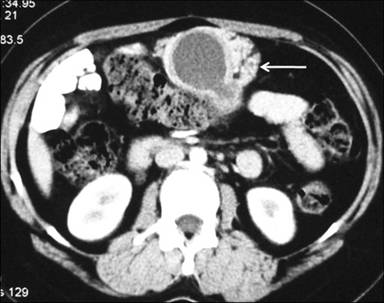

A 30-year-old woman presented with recurrent episodes of dull aching non-radiating abdominal pain of a 6 month duration which was localized in the epigastric region and was non colicky in nature with no relation to meals. It was associated with occasional non-bilious vomiting. There was no history of jaundice, gastrointestinal bleeding, melena, weight loss or altered bowel habits. There was no history of diabetes mellitus, tuberculosis, hypertension or cardiac disease. On examination, she was anicteric, had no pallor and no palpable lumps or tenderness. At admission, her hemoglobin was 11.9 g/dL (reference range: 12.0-14.0 g/dL), total leukocyte count 6,700 mm-3 (reference range: 4,000-9,000 mm-3), serum total bilirubin 0.6 mg/dL (reference range: 0.3-1.3 mg/dL), aspartate transaminase 18 IU/L (reference range: 7-41 IU/L), alanine transaminase 16 IU/L (reference range: 12-38 IU/L), alkaline phosphatase 201 IU/L (reference range: 80-290 IU/L), and serum amylase 112 IU/L (reference range: 22-80 IU/L). A contrast-enhanced CT scan showed a cystic lesion with finger-like projections abutting the pylorus and the antrum of the stomach with an adjacent stippled fat density lesion (Figures 1 and 2). Ultrasound of the abdomen showed an anechoic cystic structure with an inner hyperechoic layer and an outer hypoechoic layer which was contiguous with the muscle layer of the stomach (Figure 3), confirming the diagnosis of a duplication cyst.

|

Figure 2. Contrast-enhanced CT (axial sections) of the abdomen showing a well-defined cystic lesion surrounded, on its anterior and lateral walls, by an enhancing soft tissue mass with stippled fat density areas within (arrow), similar to pancreatic tissue. The cyst wall has a two layered appearance, with an inner thin hypodense layer and an outer enhancing layer. |